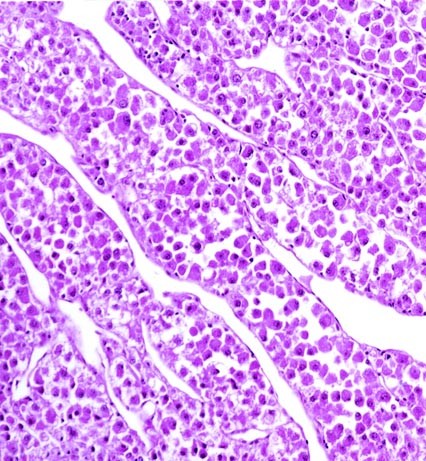

The adrenal glands of all four cases were almost completely replaced by a partially encapsulated neoplasm. Only a thin rim of residual normal adrenal gland remained. The polygonal neoplastic oncocytic cells were seen arranged predominantly in a diffuse pattern (Fig. 2). In some areas, nests and trabeculae of neoplastic cells separated by sinusoids lined by flattened endothelial cells were identified (Fig. 3). Large irregular zones of necrosis were noted. The neoplastic cells were large, round to polygonal, with round nuclei and prominent nucleoli, and abundant granular and eosinophilic cytoplasm (Fig. 4). Giant mononuclear and binucleated cells were seen in one case (case 4). Focal bizarre cytologic atypia was noted in the remaining three cases. Clusters of neoplastic cells with foamy cytoplasm were noted in two tumors (Fig. 5). There were rare mitotic figures (less than one per 10 high power fields). Vascular invasion, outside of the tumors, was identified in two cases and extra capsular extension in three tumors.